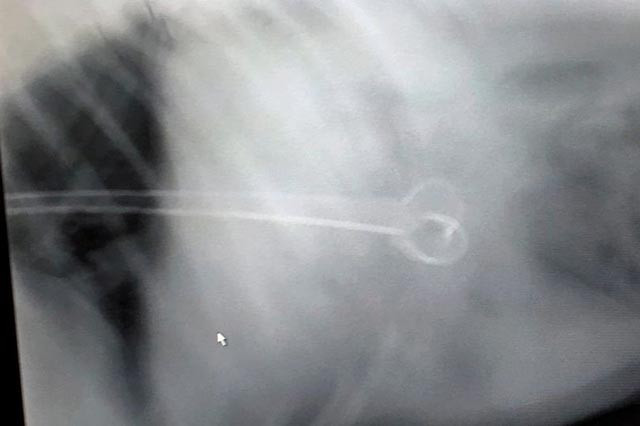

Bir anda Howie'nin ağzına bir kılıç gibi saplanan şişi gören aile derhal veterinere koştu. Howie’nin midesinden çıkarılan şişin 15 cm uzunluğunda olduğu anlaşıldı.